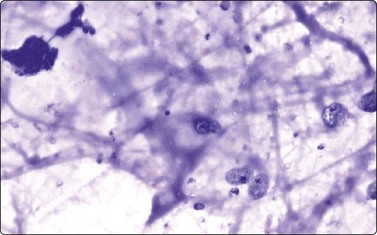

Inflammatory conditions

The cytology of lymphadenitis is described in Chapter 5. Special attention has been given to the diagnosis of sarcoid and of tuberculous lymphadenitis in the head and neck region.40 We have seen examples of actinomycosis of the parotid region and of the pharynx, clinically suspected of neoplasia due to the induration of the tissues. Sulphur granules were not seen macroscopically but microscopically a few clumps of finely filamentous microorganisms surrounded by polymorphs suggested the correct diagnosis, subsequently confirmed by culture of the aspirate (Fig. 4.5). (See also Chapter 18.)

image

Fig. 4.5 Actinomycosis

Clumps of finely fibrillar organisms in a background of neutrophils (MGG, HP).